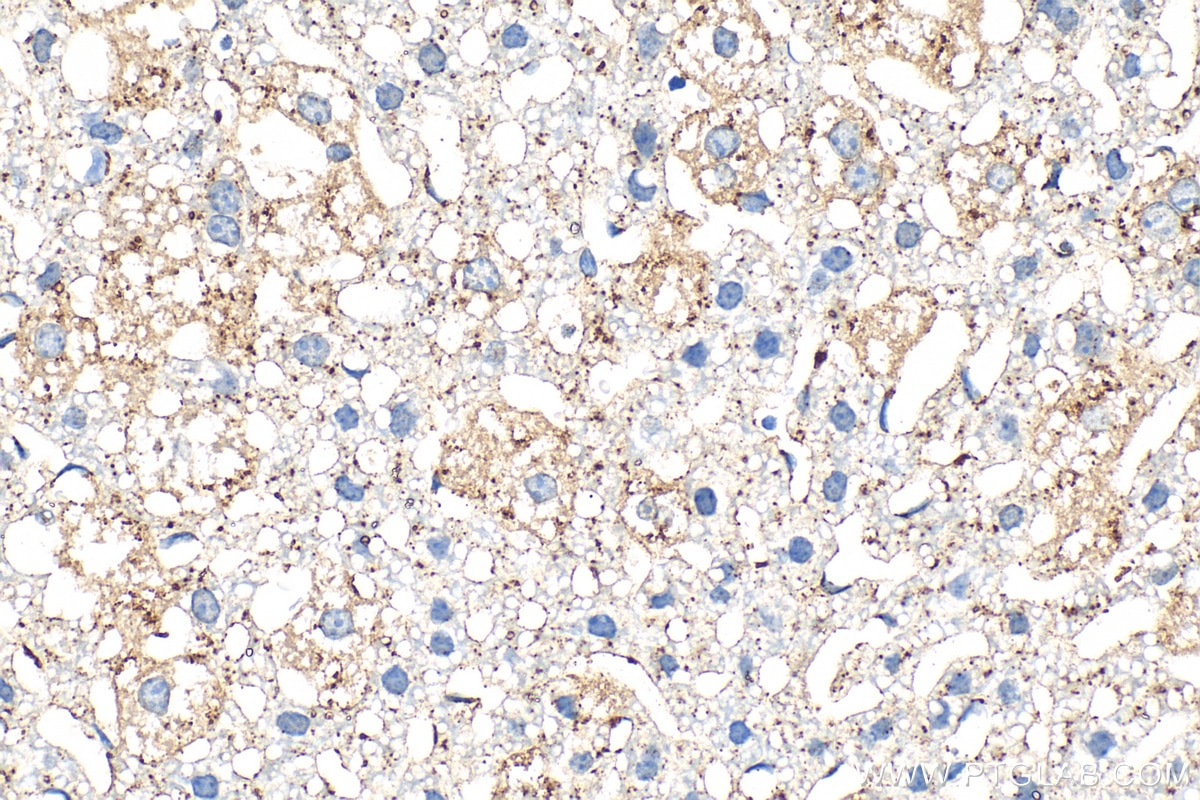

| Positive IHC detected in | human ovary cancer tissue, human liver tissue, mouse liver tissue Note: suggested antigen retrieval with TE buffer pH 9.0; (*) Alternatively, antigen retrieval may be performed with citrate buffer pH 6.0 |

| Immunohistochemistry (IHC) | IHC : 1:50-1:500 |